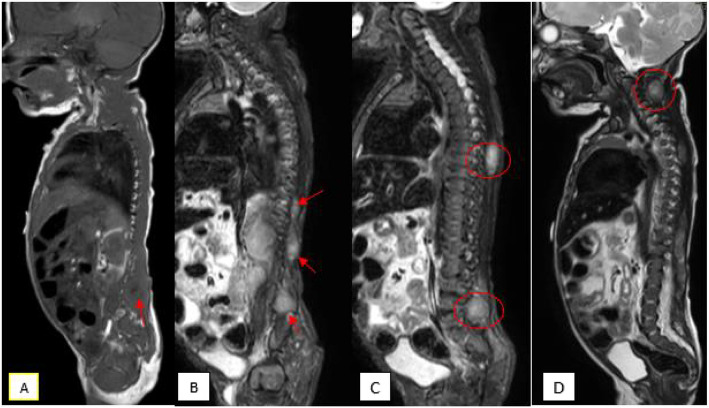

Background: Infantile myofibromatosis, a rare soft tissue neoplasm that may present at birth or in early infancy, is the most common fibrous tumor of infancy and early childhood. Diagnosis could be challenging due to different clinical presentation. Very few cases are detected prenatally and visceral involvement is extremely rare.

Case presentation: We present a case of Disseminated Infantile Myofibromatosis with challenging prenatal ultrasound and misleading clinical presentation. Diagnosis was very difficult and confirmed by pathology results obtained after birth.

Conclusions: Visceral involvement constitutes a specific unfavorable prognostic factor but a watchful waiting approach would always be appropriate, since spontaneous regression and a favourable evolution are possible and age-related chemotherapy severe side effects and long-term sequelae are matter of concern.